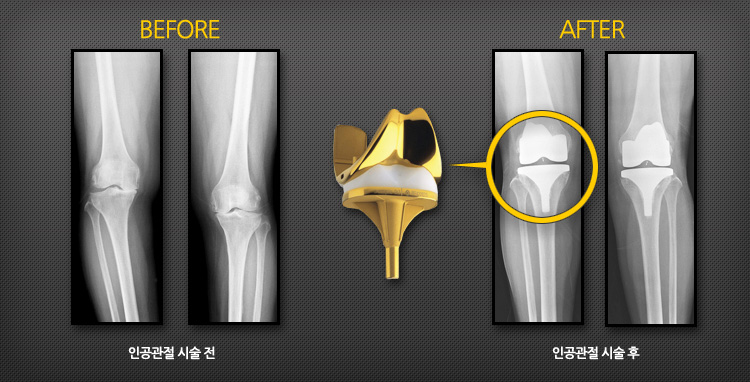

인공 슬(무릎)관절 치환술 증례

인공 슬(무릎)관절 치환술의 효과!

수술 후 대부분 관절의 통증이 없어지고, 완벽하지는 않지만 보행, 계단 오르내리기, 가벼운 운동 등의 일상생활을 무리 없이 할 수 있습니다. 인공관절의 수명은 대개 15~20년이며, 근래에는 점차적으로 기구의 수명이 연장되고 있습니다.